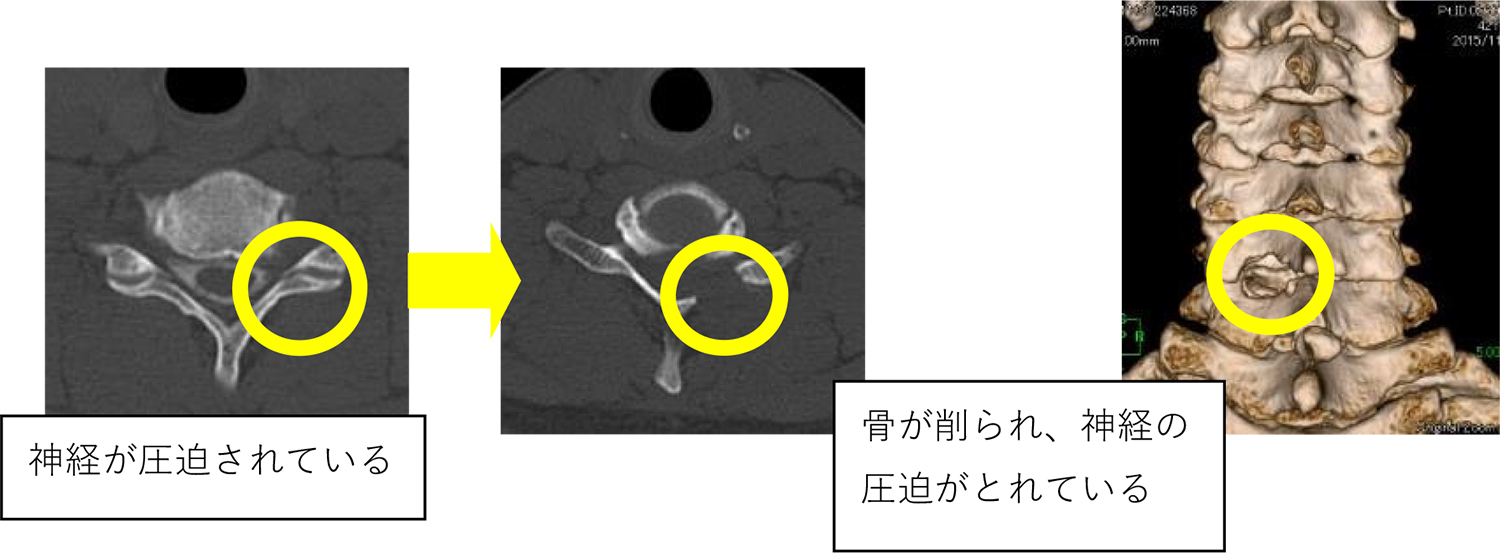

PECF法(PECF : percutaneous endoscopic cervical laminectomy : 経皮的内視鏡下頚椎椎間孔拡大術)は、8mm程度切開して、内視鏡を患部に挿入し、専用の手術器具を用いて、厚くなった靭帯や骨を切除し、圧迫された神経の除圧を行う手術です。

内視鏡により細部まで確認しながら圧迫された部位を除去できます。

PECF法は、正常な骨や筋肉、靱帯などを傷つけないようにするために考案された方法です。